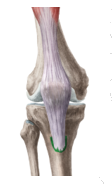

What is the structure highlighted in green?

Answer

• patella ligament

• patella tendon

• patella ligadon